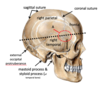

Name areas A-E

Name bones of the skull A-E

Name area A of the skull

Name vessel A